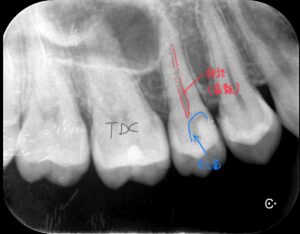

今回のケースは他院にて抜髄(神経を取る)と言われ来院した患者さんです。

歯髄(歯の神経)の反応は正常です。

レントゲン・各種診査によりVPT(Vital Pulp Therapy = 神経保存)が適応と診断しました。

術前レントゲン写真です。

レジン充填されていますが、その下に虫歯が広がっています。